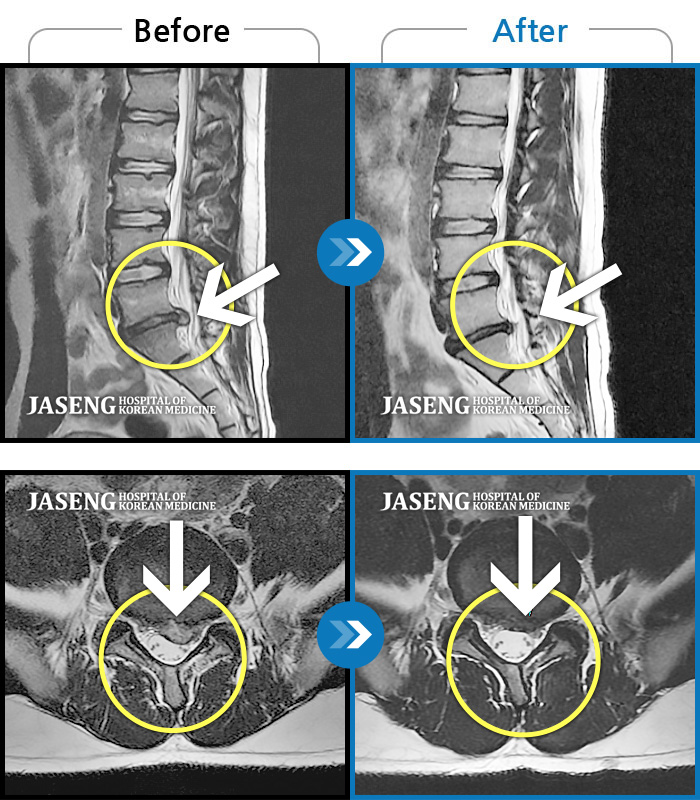

허리디스크

보라매 · 왕오호 원장

허리 통증, 똑바로 서려고 하거나 걸을 때 양쪽 허벅지와 고관절 시큰거림

촬영시기

2017.06.07 ~ 2018.04.17

2018.12.28

조회수 4,169